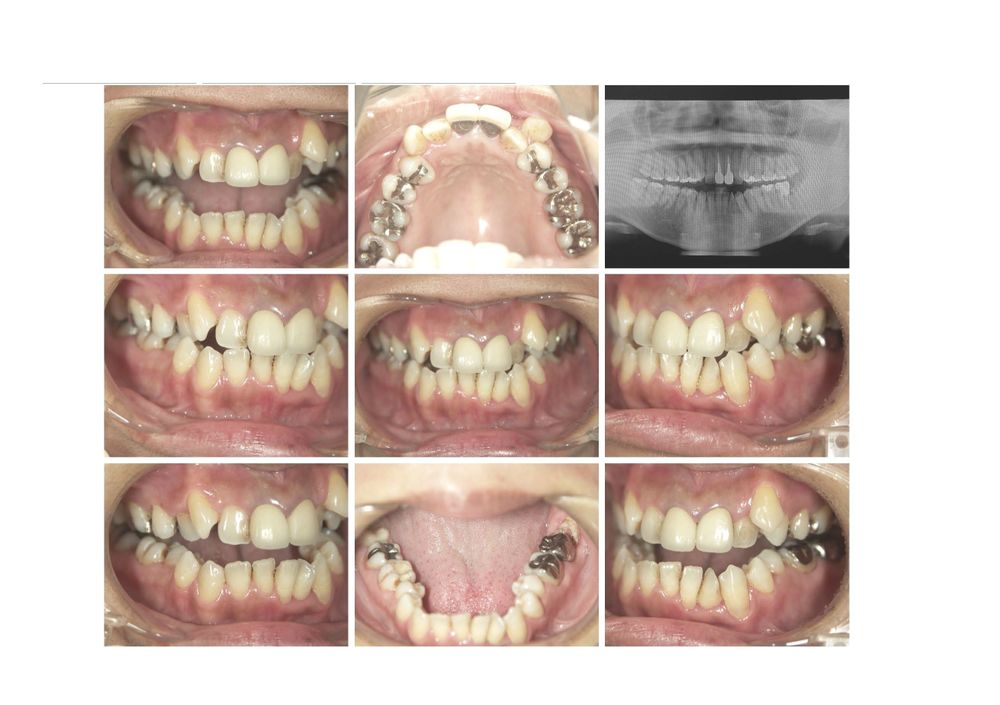

症例 2

女性 46才 1年1カ月